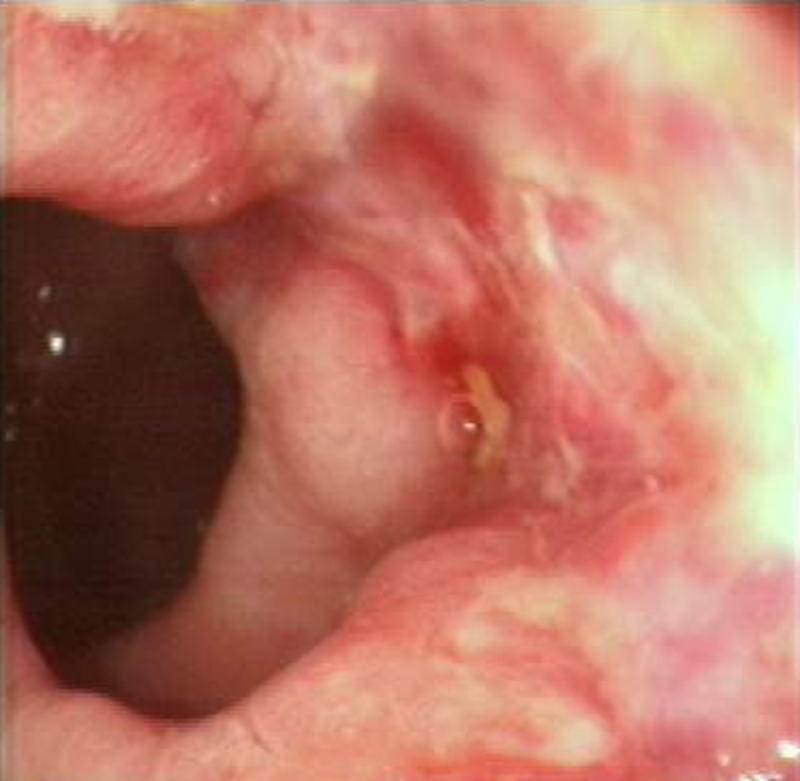

2、结直肠镜检:检查前需要口服泻药或灌肠帮助排空肠道中的粪便,作为检查的重要手段,对于部分息肉可以进行治疗,取病理组织活检是诊断结、直肠癌的金标准。但是,我国人口多,检查设备和专业医务人员少,很难全面普查。

肠镜下直肠肿瘤

肠癌隆起型

直肠癌浸润型

肠癌溃疡型